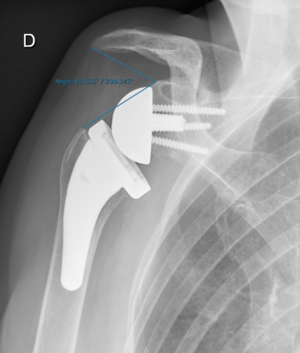

Surgical options to address malunited proximal humerus fractures are determined largely by the existing deformity. They can be categorized broadly as humeral head-preserving techniques (e.g. osteotomies, soft-tissue releases and removal of bony protuberances) or humeral head-sacrificing techniques. Amongst the latter, reverse shoulder arthroplasty proved to be the most reliable.

Reverse shoulder arthroplasty for malunion of proximal humeral fracture. A) Anteroposterior radiograph of a malunited proximal humerus fracture; B) post-operative radiograph of the fracture sequelae treated with reverse shoulder arthroplasty.